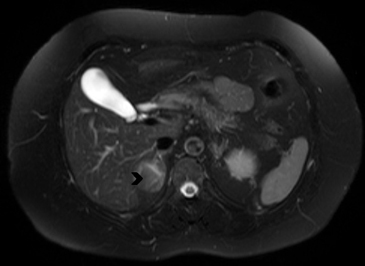

En la TC no contrastada las glándulas suprarrenales normales son homogéneas y simétricas, con una densidad muy similar a la del parénquima renal adyacente (Figura 1 a). Con un medio de contraste ev la glándula suprarrenal se opacifica en forma homogénea, similar al hígado o al bazo (Figura 1 b). Si la cantidad de tejido adiposo retroperitoneal es abundante las glándulas suprarrenales pueden aparecer enteramente rodeadas por grasa y su delimitación es más fácil (Figura 2 a); lo inverso ocurre en pacientes muy delgados con escasa grasa retroperitoneal (Figura 2 b). En RM, en secuencias ponderadas en T1 y T2 convencionales tienen una intensidad de señal homogénea, hipointensa respecto de la grasa adyacente e iso o hipointensa con respecto del parénquima hepático (Figura 3 a y b). En los cortes coronales se aprecia mejor la forma y la posición de las glándulas suprarrenales (Figura 3 c).

Figura 3. Glándula suprarrenal normal en resonancia magnética. (a) Cortes axial ponderado en T1 la señal de la glándula normal (flecha negra) es hipointensa respecto a la grasa retroperitoneal e isointensa respecto al parénquima hepático. (b) Cortes axial ponderado en T2 en que se muestra la glándula suprarrenal derecha (flecha blanca) y (c) corte coronal ponderado en T2 en que se muestra la glándula suprarrenal derecha (flecha blanca) y la glándula suprarrenal izquierda (flecha negra) con similares características de intendidad de señal. 3. Causas y prevalencia de las lesiones suprarrenales